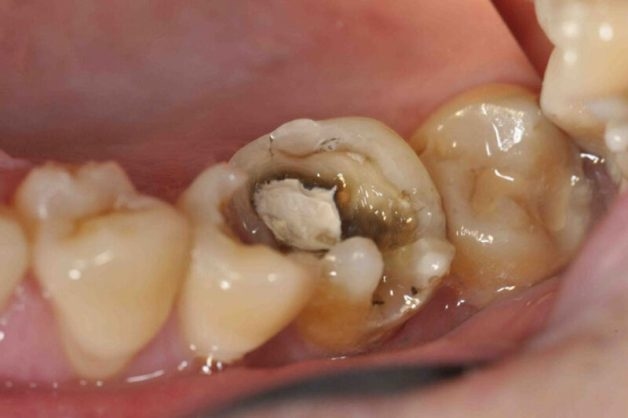

Biểu hiện của sâu răng đa dạng từ vết nâu, đen trên bề mặt đến lỗ sâu rộng ăn hết phần ngà răng

Sâu răng là bệnh lý xảy ra khi răng gặp tình trạng hủy khoáng do vi khuẩn sinh sôi gây nên, tạo thành các vệt đen hoặc lỗ nhỏ trên răng. Các khu vực tổn thương này có thể xuất hiện ở bất kỳ vị trí nào trên răng:

– Sâu ở thân răng: là loại sâu răng thường thấy nhất, xuất hiện ở cả người lớn và trẻ em. Vết sâu được xác định là ở thân răng khi xảy ra trên bề mặt nhai hoặc khe giữa các răng.

– Sâu ở chân răng: là vấn đề thường gặp ở người lớn tuổi. Tình trạng tụt nướu khi về già khiến 1 phần chân răng (bộ phận k có men răng bảo vệ) bị lộ ra ngoài chính là nguyên nhân chân răng dễ bị sâu.

Giai đoạn 2: Sâu lan mạnh vào ngà răng

Răng ở giai đoạn 1 nếu không được điều trị ngay sẽ chuyển sang giai đoạn 2, khi mà các vết sâu nghiêm trọng hơn, ăn vào ngà răng bên dưới lớp men, tạo nên cá lỗ sâu to, rộng, rất dễ mắc thực phẩm vào khi ăn, gây hôi miệng. Ngoài ra, cảm giác đau, ê buốt nặng hơn sẽ xuất hiện khi ăn nhai và ăn đồ nóng, lạnh. Đây gần như là thời điểm cuối cùng để bệnh nhân điều trị với mục tiêu bảo tồn được răng.